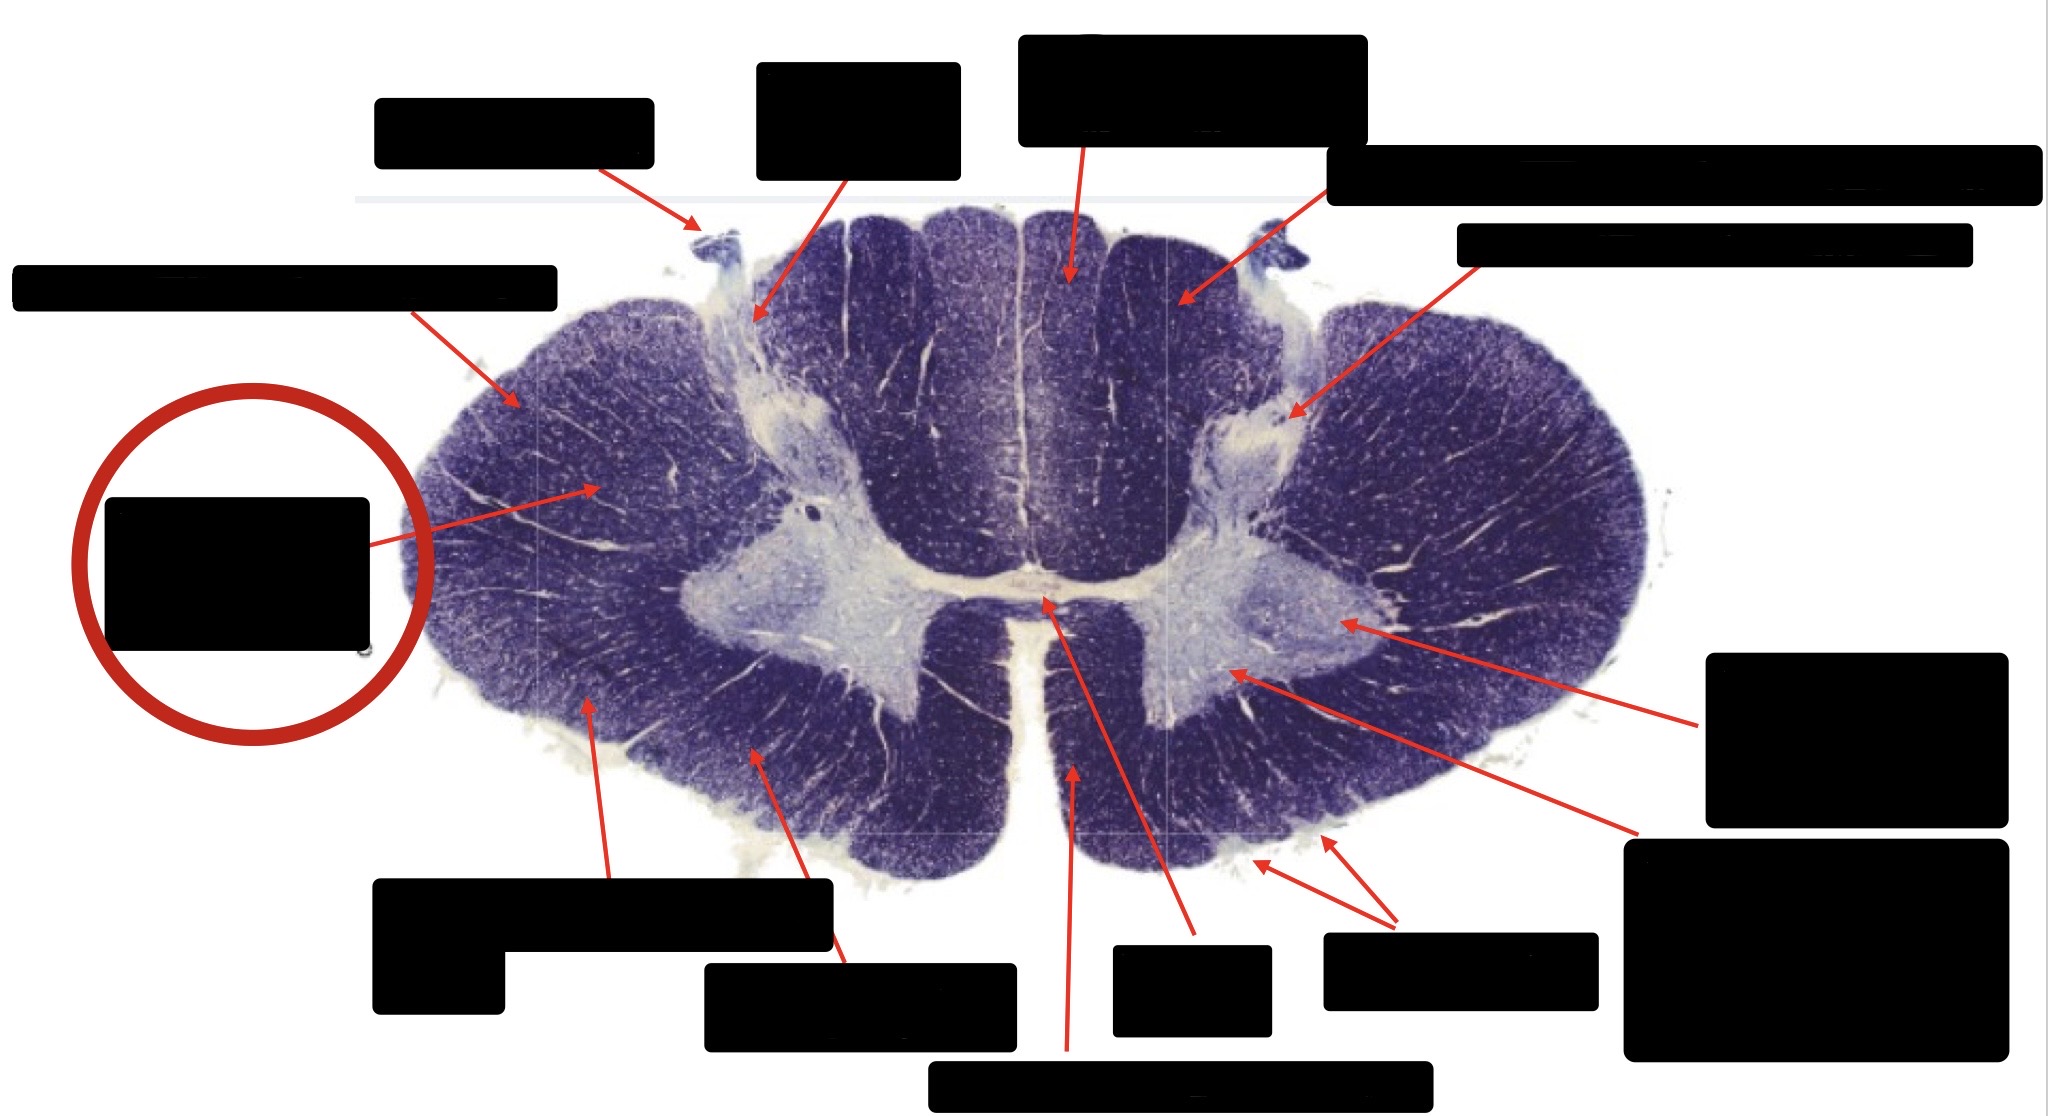

Central Canal

Anterior Corticospinal Tract

Posterior Column (Fasciculus Gracilis)

Posterior Column (Fasciculus Cuneatus)

Substantia Gelatinosa

Accessory Nerve Fibers

Anterior Horn Motor Fibers (Accessory Muscles)

Anterior Horn Motor Fibers (Proximal Muscles)

Ventral Root Fibers

Anterior Horn Motors Neurons (Proximal Muscles)

Posterior Columns (Joint Position, Vibration, Pressure)

Fasciculus Cuneatus

Fasciculus Gracilis

Dorsal Root

Dorsal Spinocerebellar Tract

Ventral Spinocerebellar Tract

Lateral Spinocerebellar Tract (Pain & Temperature)

Ventral Root

Anterior Horn (Motor Neurons)

Distal Limb Movements

Lateral Corticospinal (Pyramidal Tract)

Rubrospinal Tract

Axial & Proximal Limb Movements

Lateral Reticulospinal Tract

Vestibulospinal Tract

Ventral Reticulospinal Tract

Tectospinal Tract

Ventral Spinthalamic Tract (Pressure Touch - Minor Role)

Ventral (Uncrossed) Corticospinal Tract (Distal Limb Movements - Minor Role)